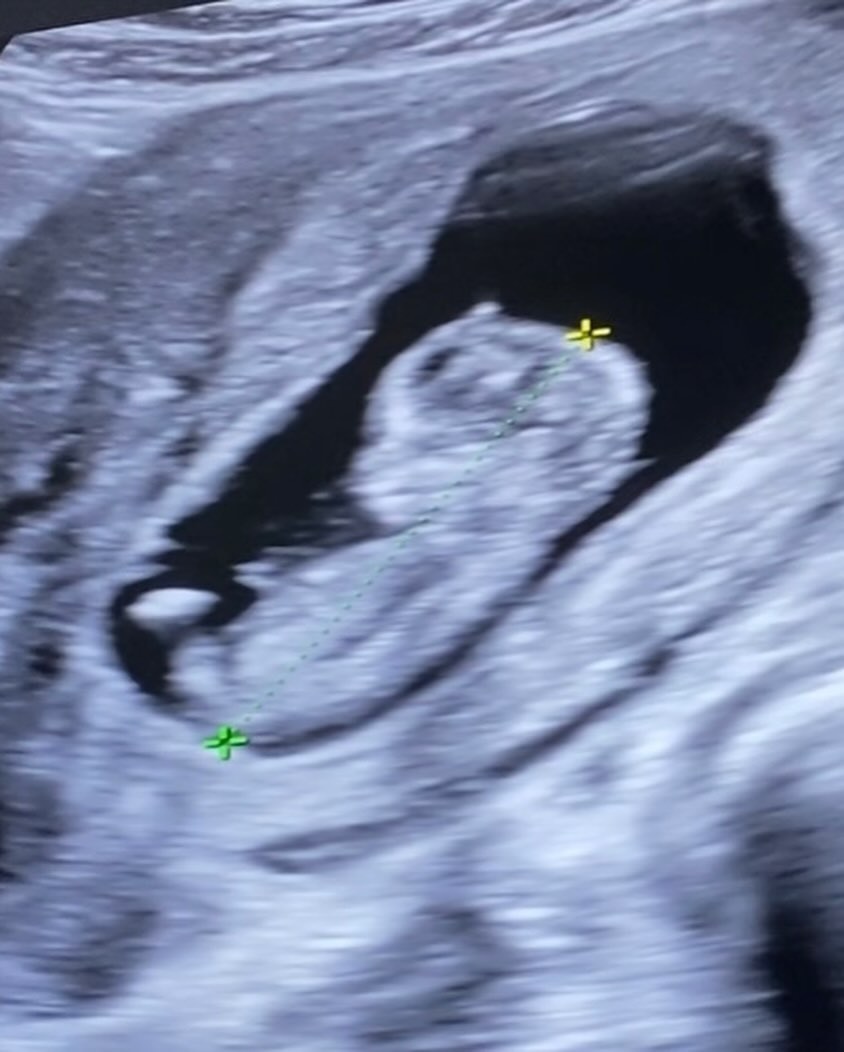

เป็นสมาชิกวงบอยแบนด์ในตำนานที่หลายคนยังคงคิดถึง แถมยังมีดีกรีเป็นอดีตพระเอกดัง สำหรับ เปปเปอร์ UHT หรือ เปปเปอร์ รัฐศาสตร์ ที่ล่าสุด (27 ธันวาคม 2567) ได้ออกมาประกาศข่าวดีหลังแต่งงาน 4 ปี เตรียมตัวเป็นคุณพ่อแล้ว หลังภรรยาสาว ดรีม ศุภากร ตั้งท้องลูกคนแรก